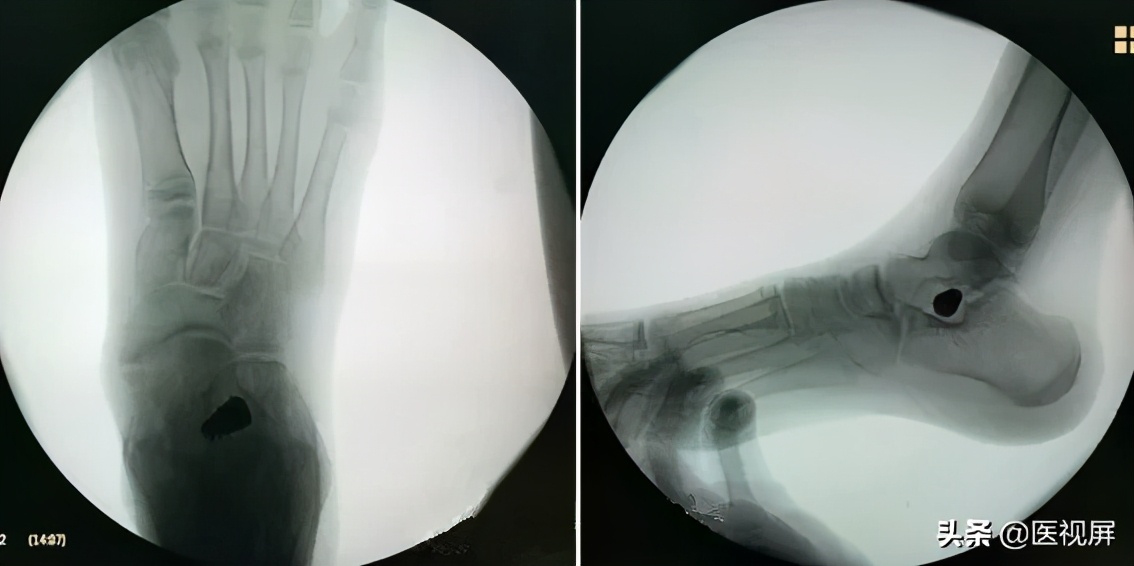

取出试模,打入相同大小型号的距下关节制动器。再次透视确认制动器位置(图6)。

▲图6 置入距下关节制动器

女性12岁

行双侧距下关节制动术

术后一年随访:术后后跟内翻纠正,足弓抬高(图7)。

▲图7 术后病例